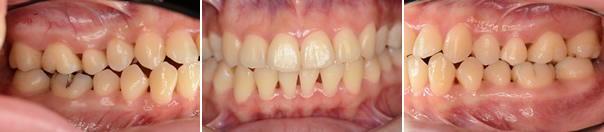

歯周形成外科 結合組織移植

エムドゲインによる歯周組織再生療法

Before

After

| 主訴 | 下の歯の歯肉が下がっていている |

|---|---|

| 治療期間 | 約1ヶ月 |

| 費用 | 120,000円 |

| デメリット・注意点 | 術後に腫れる可能性がある。 |